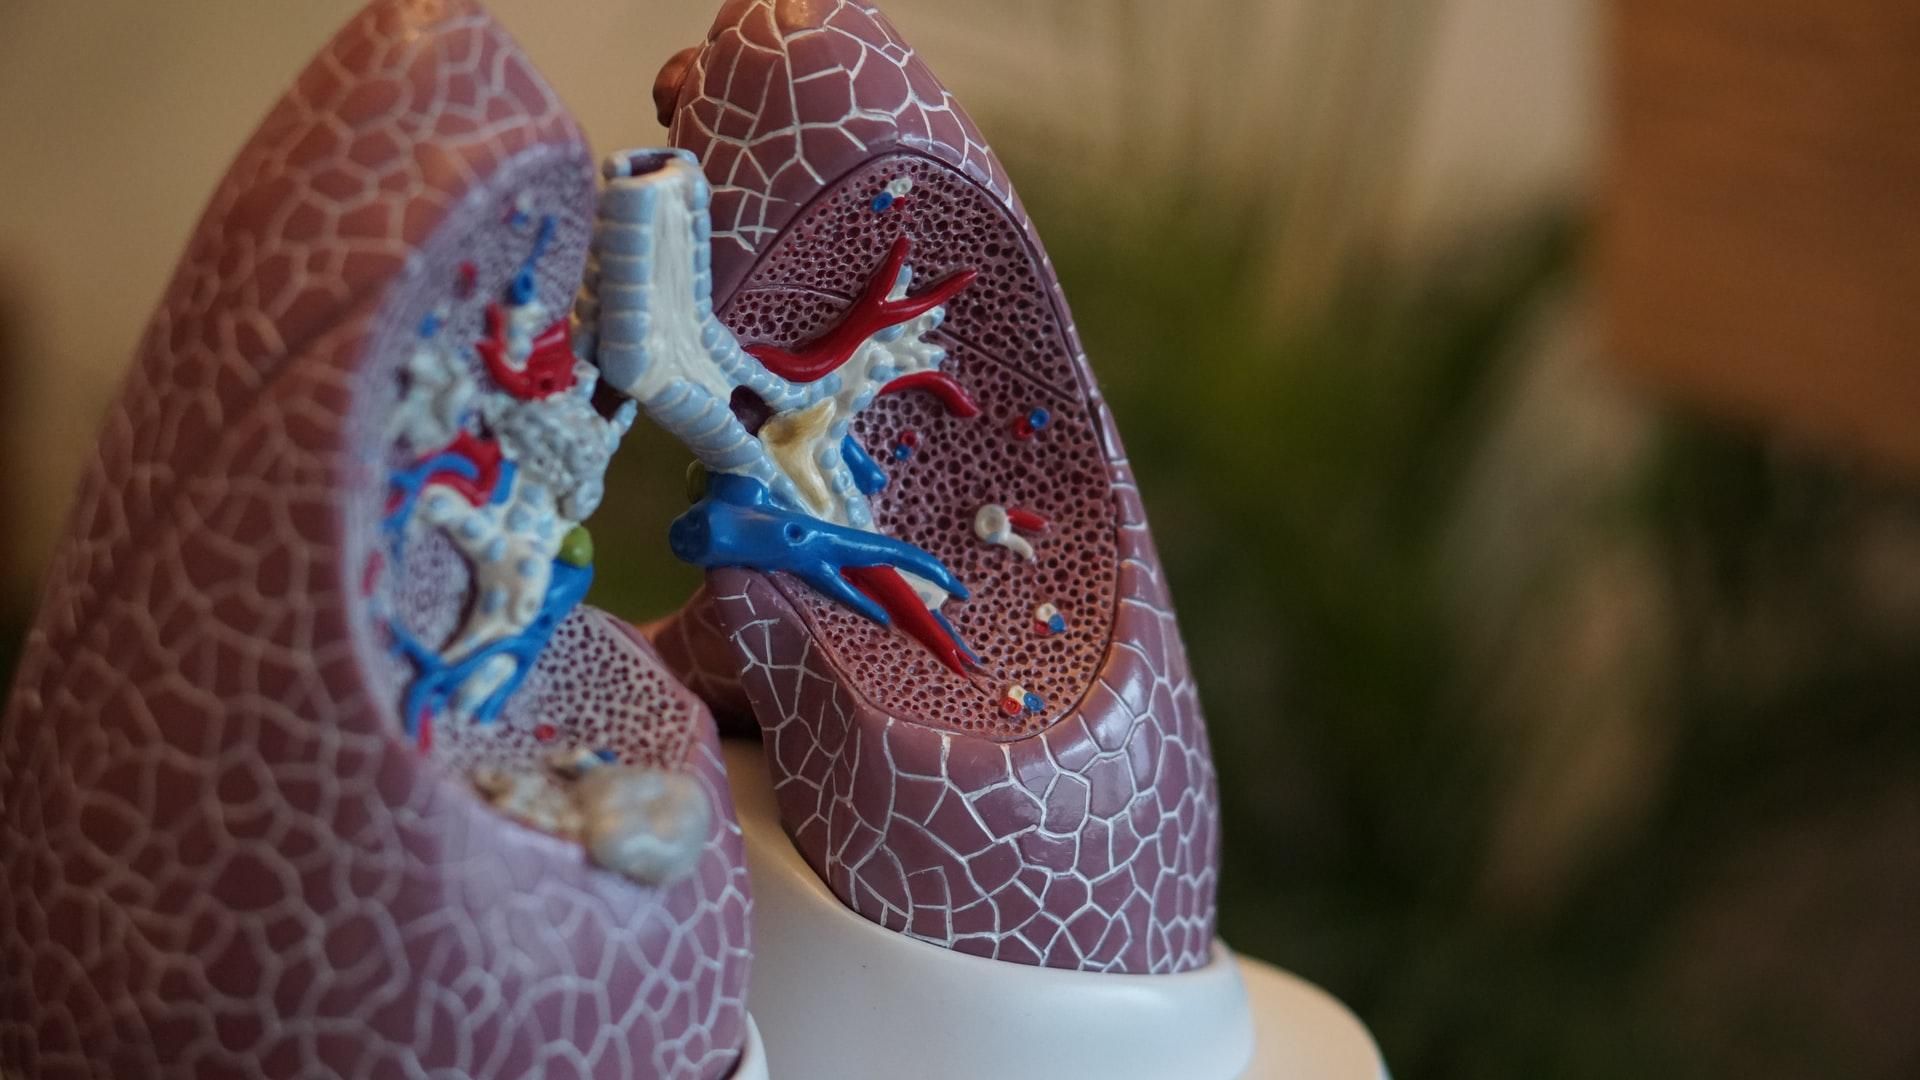

Як працюють легені

Наші легені є дуже важливим органом, основна функція якого – газообмін. Тобто завдяки легеням наша кров насичується киснем та повертає назад вуглець або вуглекислий газ. Відбувається газообмін в альвеолах, до яких повітря доходить по бронхіальному дереву.

Наші легені досить гнучкі й можуть звужуватись та розширюватись залежно від ситуації. Наприклад, коли повітря тепле або займаємось фізичною активність – бронхи розширюються, йде форсоване дихання і ми споживаємо більше повітря та кисню, тож можемо виконувати фізичну роботу.